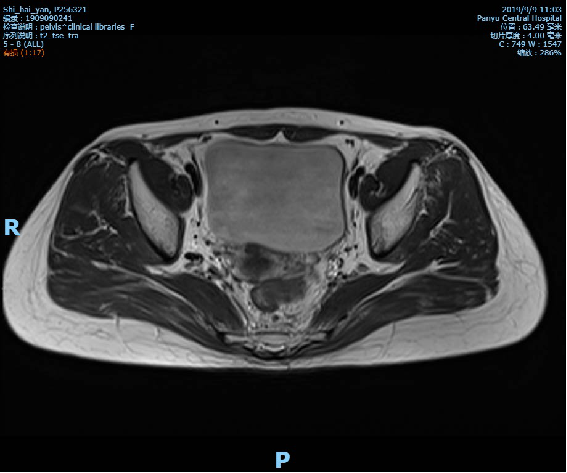

2019-10-09复查盆腔MR示直肠全段管壁不均匀增厚,以中段较明显,最厚处约11mm,较前相仿,仍考虑直肠癌累及浆膜面,较前略有好转,不除外直肠前筋膜受累;胸腹CT未见转移征象。

术前影像学检查: